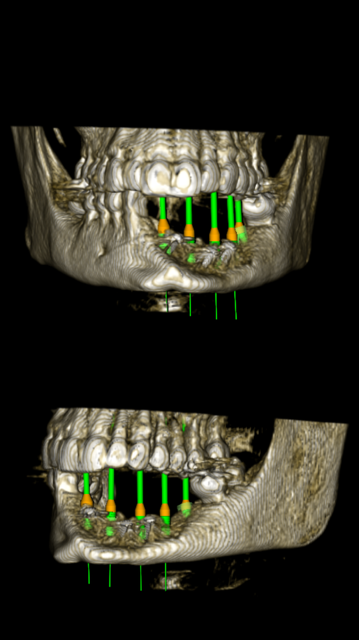

In anticipation of the second tumor, Kim is still needing to address the reconstruction of the removal of the original tumor. At this stage, one-year post surgery, the plan is to begin the preparation for porcelain implants, or a new set of teeth. In order to do this, Kim will face a third surgery in which five metal posts will be implanted into the graphed bone in her jaw. This surgery cost is roughly $9,795. However, the quote only includes 30 minutes of general anesthesia, and the doctors anticipate surgery could take up to an hour and a half.

Following the third surgery, if all goes as planned, it should take about 4-6 months of tissue recovery before Kim faces another surgery in which the surgeon will re-expose the five metal posts and cap them in order to prevent further tissue growth. Once the posts are capped, Kim will face another 4-6 months of healing. This fourth surgery has yet to be quoted, but given previous experiences it is only fair to assume that it will be costly.

In anticipation of the second tumor, Kim is still needing to address the reconstruction of the removal of the original tumor. At this stage, one-year post surgery, the plan is to begin the preparation for porcelain implants, or a new set of teeth. In order to do this, Kim will face a third surgery in which five metal posts will be implanted into the graphed bone in her jaw. This surgery cost is roughly $9,795. However, the quote only includes 30 minutes of general anesthesia, and the doctors anticipate surgery could take up to an hour and a half.

Following the third surgery, if all goes as planned, it should take about 4-6 months of tissue recovery before Kim faces another surgery in which the surgeon will re-expose the five metal posts and cap them in order to prevent further tissue growth. Once the posts are capped, Kim will face another 4-6 months of healing. This fourth surgery has yet to be quoted, but given previous experiences it is only fair to assume that it will be costly.